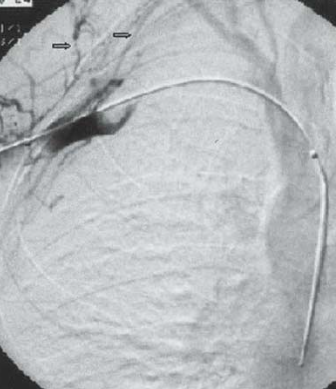

• TVP du MS chez patients avec efforts ++ du MS (Sportive, professionelle)

• Favorisé par une compression de type Défilé Thoracique (cote cervicale, rétrecissement costoclaviculaire, etc.)

• Collatérales veineuses

• TTT: medicaments thrombolytiques (peut être fait en interventionnel)

e2fba715c3cdeb1fd7ec882c43a4949f.png 3f15f7297f83d687cb3807c0b5286896.png 12cb667e7bab1d45a2a5acf339e31acc.pngpaget schrotter schroetter shor shroette schro¨tter schrötter schroiet schroeter sportif sprotifs